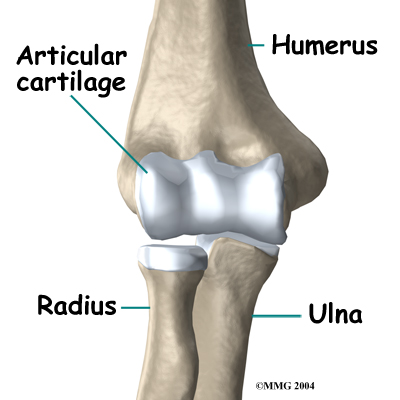

The elbow is the connection of the upper arm bone (the humerus) and the two bones of the forearm (the ulna and the radius). The radius runs from the outer edge of the elbow down the forearm to the thumb side of the wrist.

The joint where the humerus meets the radius is called the humeroradial joint. This joint comprises a bony knob and a shallow cup. The knob on the end of the humerus is called the capitellum. The capitellum fits into the cup-shaped end of the radius. This cup is called the head of the radius.

When the head of the radius spins on the capitellum, the forearm rotates to turn the palm up toward the ceiling (supination) or down toward the floor (pronation). The joint also hinges as the elbow bends and straightens.

In the elbow joint, the ends of the bones are covered by articular cartilage — a slick, smooth, fibrous material. Articular cartilage protects the bone ends from creating friction when they rub together as the elbow moves. The cartilage is also soft enough to act as a shock absorber. If articular cartilage is protected from injury, it is robust enough to last a lifetime.

Elbow OCD affects the articular cartilage in the capitellum. It also impacts the layer of bone just below the cartilage, which is called the subchondral bone. In advanced stages of OCD, the upper end of the radius, particularly the head of the radius, is also affected.